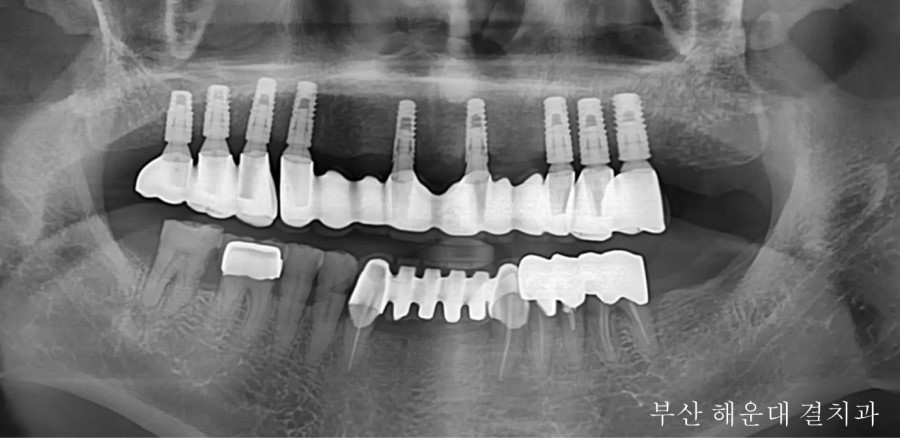

다음 환자는 상악 잔존치아가 파절 되어 발치 후 틀니로 치료를 진행하셨지만, 4개월 만에 불편함과 여러 가지 이유로 임플란트가 가능한지 문의해 오셧습니다.

상담후 9개의 임플란트를 식립하고 고정성 보철물(틀니와 다르게 입안에 고정되어있는 보철)로 진행하기로 하였습니다.

발치 후 임플란트 식립 사진입니다. 역학적으로 꼭 필요한 부위에만 임플란트를 식립하고, 사이에 비어있는 공간은 '브릿지 보철'로 수복 할 수 있도록 게획하였습니다.

추가적으로 뼈가 부족한 부위에는 '골이식(뼈이식)'을 시행하였습니다.